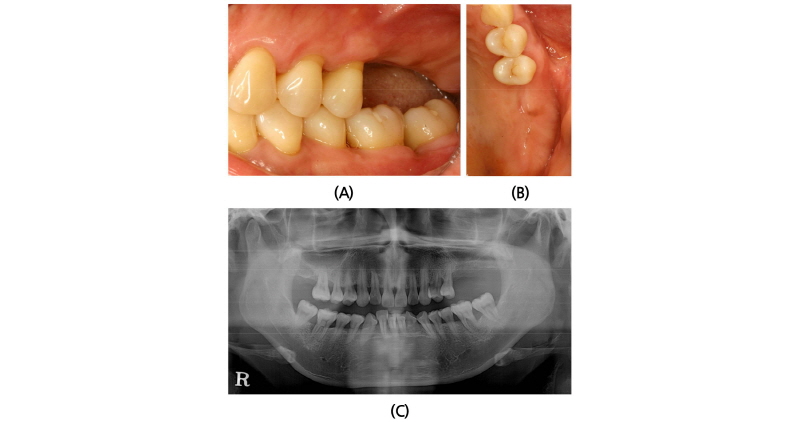

A 45-year old female patient who had missing teeth of first (#26) and second molar (#27) in left maxilla visited the clinic to plan for the reconstruction of both molars (Fig. 1). The edentulous ridge had sufficient buccopalatal width and the vertical dimension was about 8 mm from the soft tissue level (Fig. 1A, 1B). The patient was diagnosed as generalized chronic moderate periodontitis and received nonsurgical periodontal treatment prior to the surgery. In addition, regenerative therapy using bone graft materials was prepared in the intrabony defect of right mandibular first molar (#46). The missing maxillary molars were decided to be placed with implants and the panoramic view showed deficient RBH at #26 and #27 with sinus pneumatization (Fig. 1C). In computed tomography, RBH at #26 and #27 was measured to be 5 mm and 6 mm, respectively, and SFE spontaneously with implant placement using hybrid technique was planned (Fig. 2). Flap including the midcrestal incision and vertical incision at #25 distal line angle was reflected (Fig. 3A), and linear osteotomy was prepared with a piezoelectric device (Piezosurgery®, Mectron, Carasco, Italy) (Fig. 3B). Mesiodistal width of the osteotomy was about 10 mm to include both implantation site planned for #26 and #27, and was positioned about 7~8 mm from the crest paralleled along the sinus floor. Detachment of the Schneiderian membrane was limited in the internal surface of the floor and a serial drilling one step before the final diameter was done under the protection of the membrane with the sinus elevator inserted through the linear osteotomy site (Fig. 3C). Biphasic calcium phosphate (MBCP®, Biomatlante, Vigneux de Bretagne, France) of 0.5 g was grafted via lateral opening and pushed into the floor with osteotomes and final drilling was done. Straumann SLA® (Institute Straumann AG, Waldenburg, Switzerland) diameter 4.8 RN and 10 mm length implant was installed at both #26 and #27 (Fig. 3D). Non-submerged healing with healing abutment connection was done (Fig. 3E) and the stitches were removed after 10 days (Fig. 3F). Dome-shaped radiopacity surrounding the implant apex penetrated into the floor was shown immediately after the surgery (Fig. 4A) and the prosthetic delivery was done within 3 months of healing periods. Augmented sinus floor was maintained through the 6-year of follow-up (Fig. 4B).